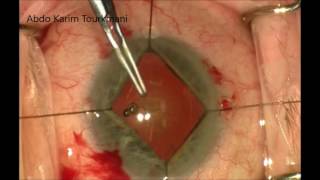

Challenging case : Small pupil & very dense cataract and Tips for IRIS Hooks - Dr. Deepak Megur Iris hooks for small pupil - Stop and chop phaco with IOL. Abdo Karim Tourkmani, FEBOphth

Challenging case : Small pupil & very dense cataract and Tips for IRIS Hooks - Dr. Deepak Megur Iris hooks for small pupil - Stop and chop phaco with IOL. Abdo Karim Tourkmani, FEBOphth